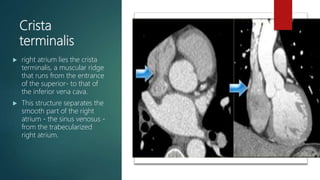

Crista

terminalis

 right atrium lies the crista

terminalis, a muscular ridge

that runs from the entrance

of the superior- to that of

the inferior vena cava.

 This structure separates the

smooth part of the right

atrium - the sinus venosus -

from the trabecularized

right atrium.